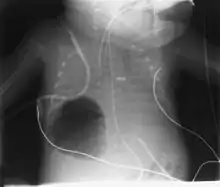

Diagnosis can be made using chest X-ray; the lesion shows up as a small, round area filled with air.[1] Computed tomography can give a more detailed understanding of the lesion.[1] Differential diagnoses – other conditions that could cause similar symptoms as pneumatocele include lung cancer, tuberculosis,[7] and a lung abscess[1] in the setting of hyper IgE syndrome (aka Job's syndrome), as a complication of COVID-19 pneumonitis,[8] or on its own, often caused by Staphylococcus aureus infection during cystic fibrosis.